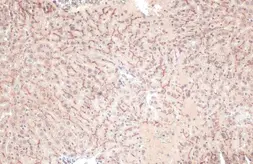

Description Rabbit MonoclonalApplications IHC-PReactivity HuSummary Highly recommended for IHC-P in human tissues.